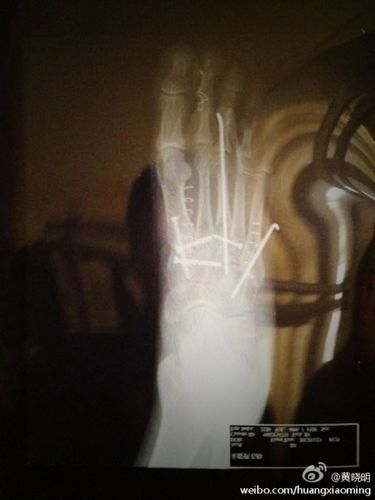

黄晓明晒有钢钉脚部X光照 配俏皮对话调侃(图)

中新网12月6日电 近日,黄晓明因脚部粉碎性骨折而在家休养,百无聊赖的他晒出一张疑似是自己脚部X光片的图,并配以俏皮对话调侃现在生活,他写道:“钢钉A:整天贴着地面的感觉真不好。钢钉B:哥,等他穿上鞋子吧……到时就怕你畏高。”

此图一发便引起关注他的网友热议,有网友称他笑话“好冷”,还有网友表示,”说实话...有点吓人...愿早日康复”,并调侃他“晓明哥哥,养病还这么闹,大概只有现在这个时候你才能这么悠哉吧 ”。